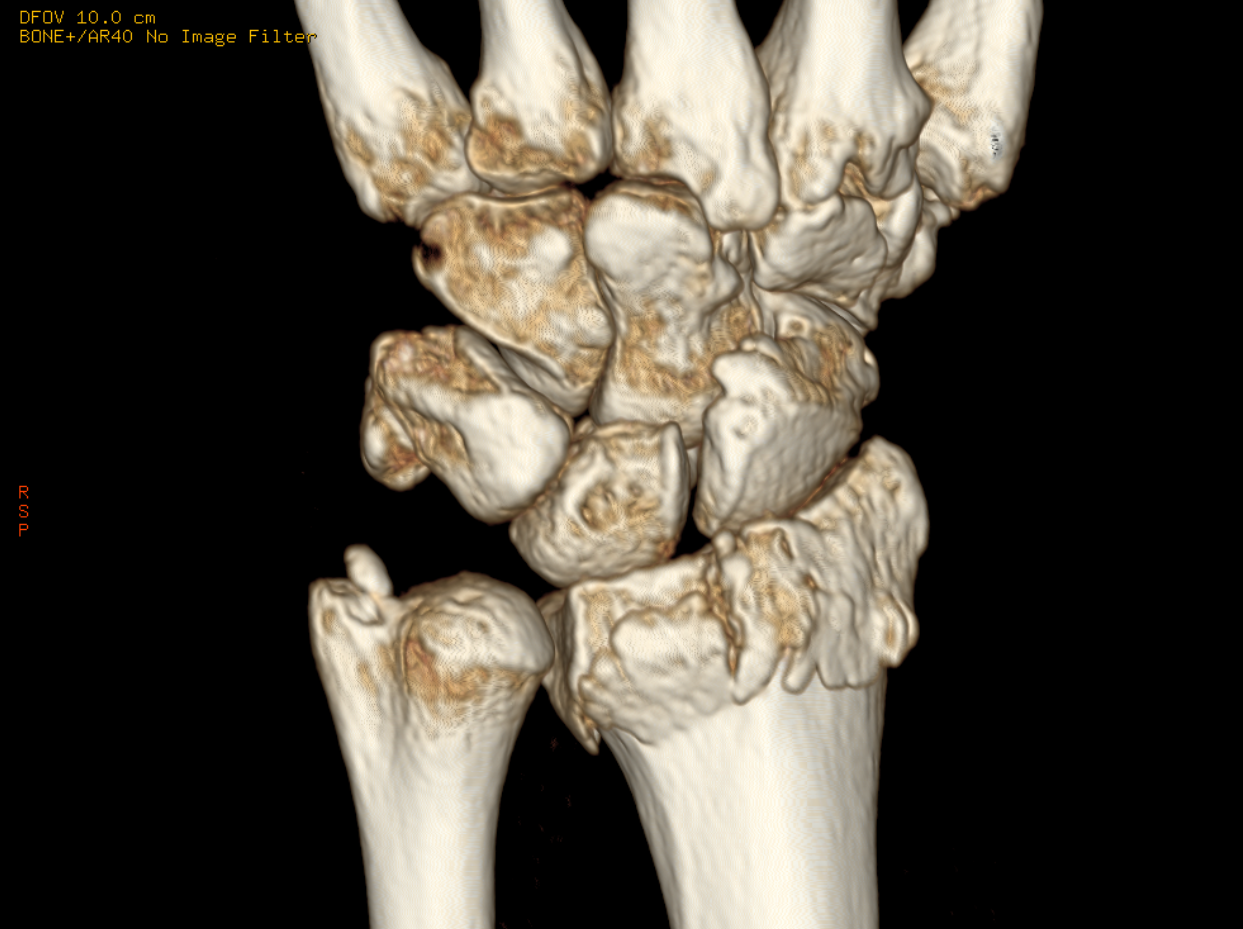

CT / MRI

◯ CTならびにMRI検査は当ビル1階のセントラルCIクリニックに依頼し、放射線科医による専門的な診断を得ています。